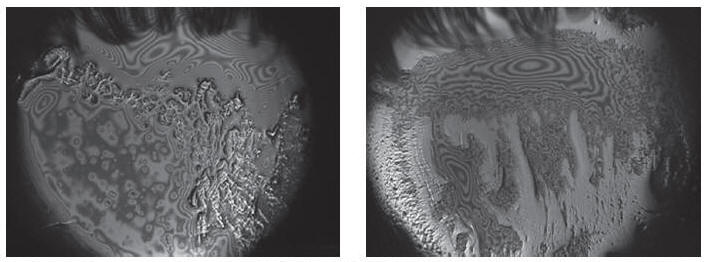

Интерферометрия слёзной пленки

Технология позволяет оценить полноценность липидного слоя слёзной пленки, предохраняющего слезу от избыточного испарения.

Процедура не инвазивна и длится менее пяти минут.